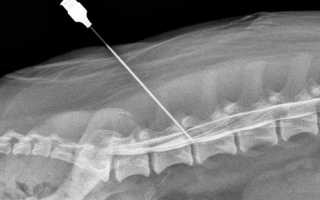

Блокада представляет собой временное отключение одного из звеньев, которые вызывают болевой симптом. Проводится такая процедура при помощи введения уколом анестетика в определенные точки позвоночника человека.

Проводниковые блокады воздействуют на нервные волокна, а процесс введения лекарства может быть эпидуральным, перидуральным, периневральным и параневральным. Ганглионарные уколы делаются непосредственно в нервные сплетения и узлы.

Не все виды блокад можно проводить таким способом. Для проведения эпидуральной блокады, используется шприц с иглой, длина которого составляет 6 сантиметров.